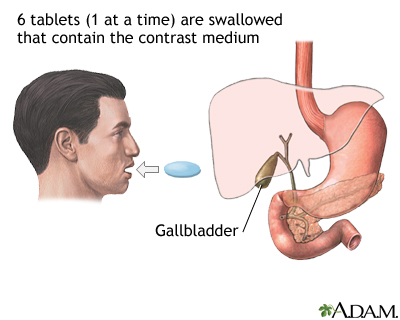

Tests that reveal gallstones or inflammation in the gallbladder include:

- Oral cholecystogram (rarely done)